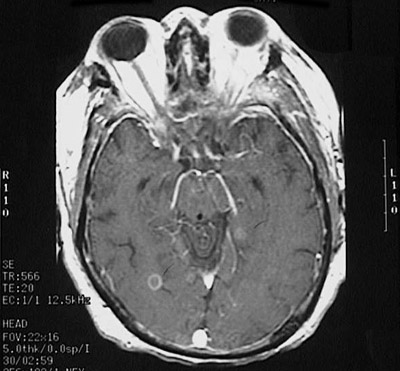

Click on the cerebral abscess in the MRI scan below:

This magnetic resonance imaging (MRI) scan of the head in transverse (axial) view demonstrates a small abscess in the brain in a patient who had septicemia.